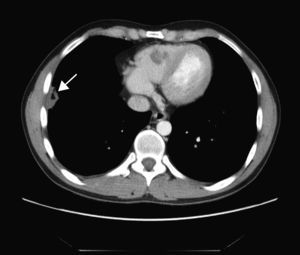

TAC toraco-abdominal: en el pulmón derecho se identifican 4 lesiones; la de mayor tamaño es muy organizativa y se encuentra adyacente a la cisura mayor-menor y otra lesión parenquimatosa en el lóbulo inferior adyacente a la cisura menor y que podría mostrar una pequeña cavitación (fig. 4). En el lóbulo inferior derecho aparecen 2 nódulos espiculados y una pequeña lesión parenquimatosa de localización muy posterior.

Angio-TAC pulmonar: se visualizan trombos de aspecto crónico en la arteria del lóbulo inferior derecho y en arterias segmentarias basales de dicho lóbulo inferior y en alguna arteria segmentaria basal izquierda. También aparecen pequeñas lesiones parenquimatosas de localización periférica en base derecha, que pueden corresponder a infartos pulmonares, y una pequeña cantidad de fluido lobulado en la confluencia de las cisuras menor y mayor derechas.

El paciente ingresa por síndrome general, tos y fiebre. Se procede al aislamiento respiratorio por sospecha de tuberculosis. Tras el estudio analítico y radiológico se descarta la posibilidad infecciosa. Se realiza una angio-TAC de arterias pulmonares que muestra una tromboembolia pulmonar múltiple, por lo que se procede a la anticoagulación.